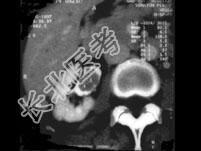

- 单项选择题男,74岁, 间歇性无痛性全程血尿2月余,尿路造影及CT平扫+增强如图所示, 下列说法错误的是 ( )

C、增强扫描示右侧肾盂内软组织块影轻度强化

D、考虑为右侧肾盂癌

E、考虑为右侧肾盂内血块